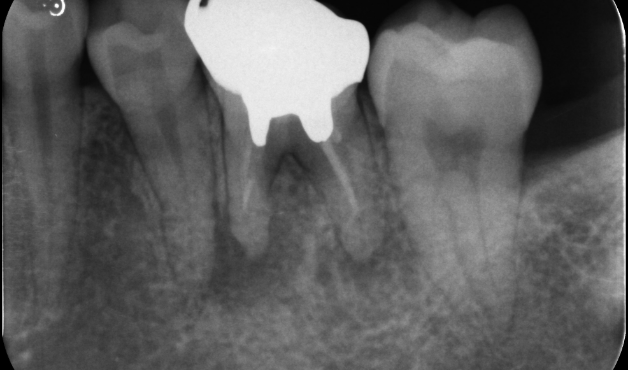

長期予後を見越した根管治療の症例

タップで写真の拡大ができます。

Before

After

主訴

症状はないが、治療が必要な箇所があればしっかり治療しておきたい。

治療内容

イニシャルトリートメント(根管治療・大臼歯)、ファイバーポストコア、セラミッククラウン

治療期間

3ヶ月

治療費用

352,000

治療の

リスク

根尖部透過像が完全に消失しない可能性があります。